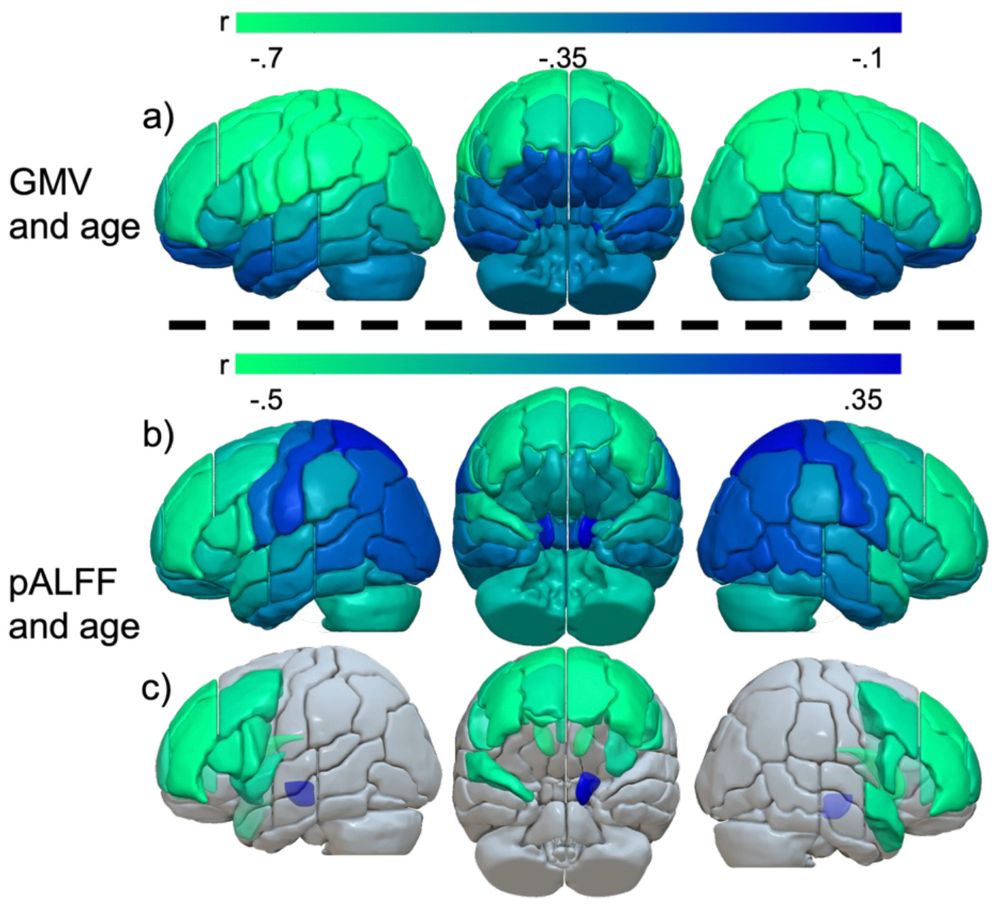

Temporoparietal brain structures support sentence processing across the adult lifespan

doi.org/10.1162/IMAG...

Temporoparietal brain structures support sentence processing across the adult lifespan

doi.org/10.1162/IMAG...